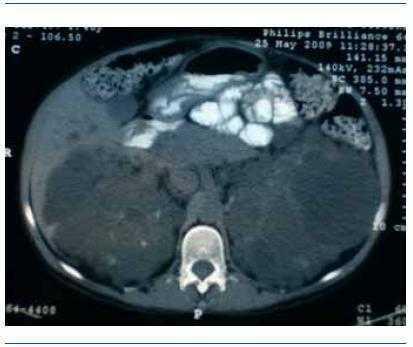

Mujer de 46 años, con antecedentes familiares de enfermedad poliquística del adulto, que ingresó por insuficiencia renal avanzada, con creatinina sérica de 8 mg/dl y clínica urémica. En la exploración abdominal se palpaban dos masas gigantes polilobuladas en ambos flancos. La ecografía abdominal mostró riñones poliquísticos y múltiples quistes hepáticos de diferentes tamaños. Durante el ingreso presentó un cuadro febril con dolor abdominal en fosa ilíaca derecha, por lo que, ante la sospecha de quiste renal complicado, se solicitó un TAC tóraco-abdominal, que mostró la existencia de una imagen ovoidea de 8,4 x 2,1 cm, hipodensa, adyacente al lado izquierdo del pericardio, compatible con quiste pericárdico. Un ecocardiograma demostró la presencia de un derrame pericárdico leve asociado. Ante la presencia de un cultivo de orina positivo para Escherichia coli, se inició tratamiento antibiótico y remitieron la fiebre y el dolor. Actualmente la paciente está en programa de hemodiálisis periódica.

Figura 2. Poliquistosis renal